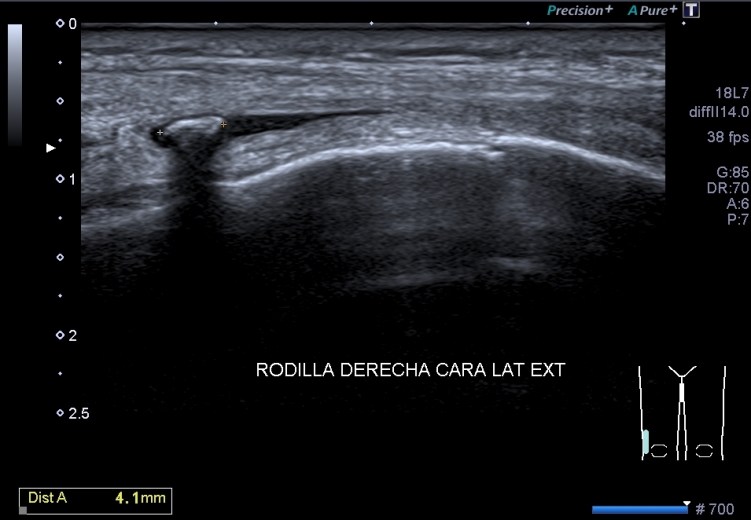

Un breve recuerdo anatómico de la zona tanto en eje largo como en eje corto (longitudinal o transverso), fig 3 y 2 respectivamente, . Fíjese la/el lectora en el posicionamiento del pictograma de referencia.

Acto seguido procedo a las mediciones en ambos planos: